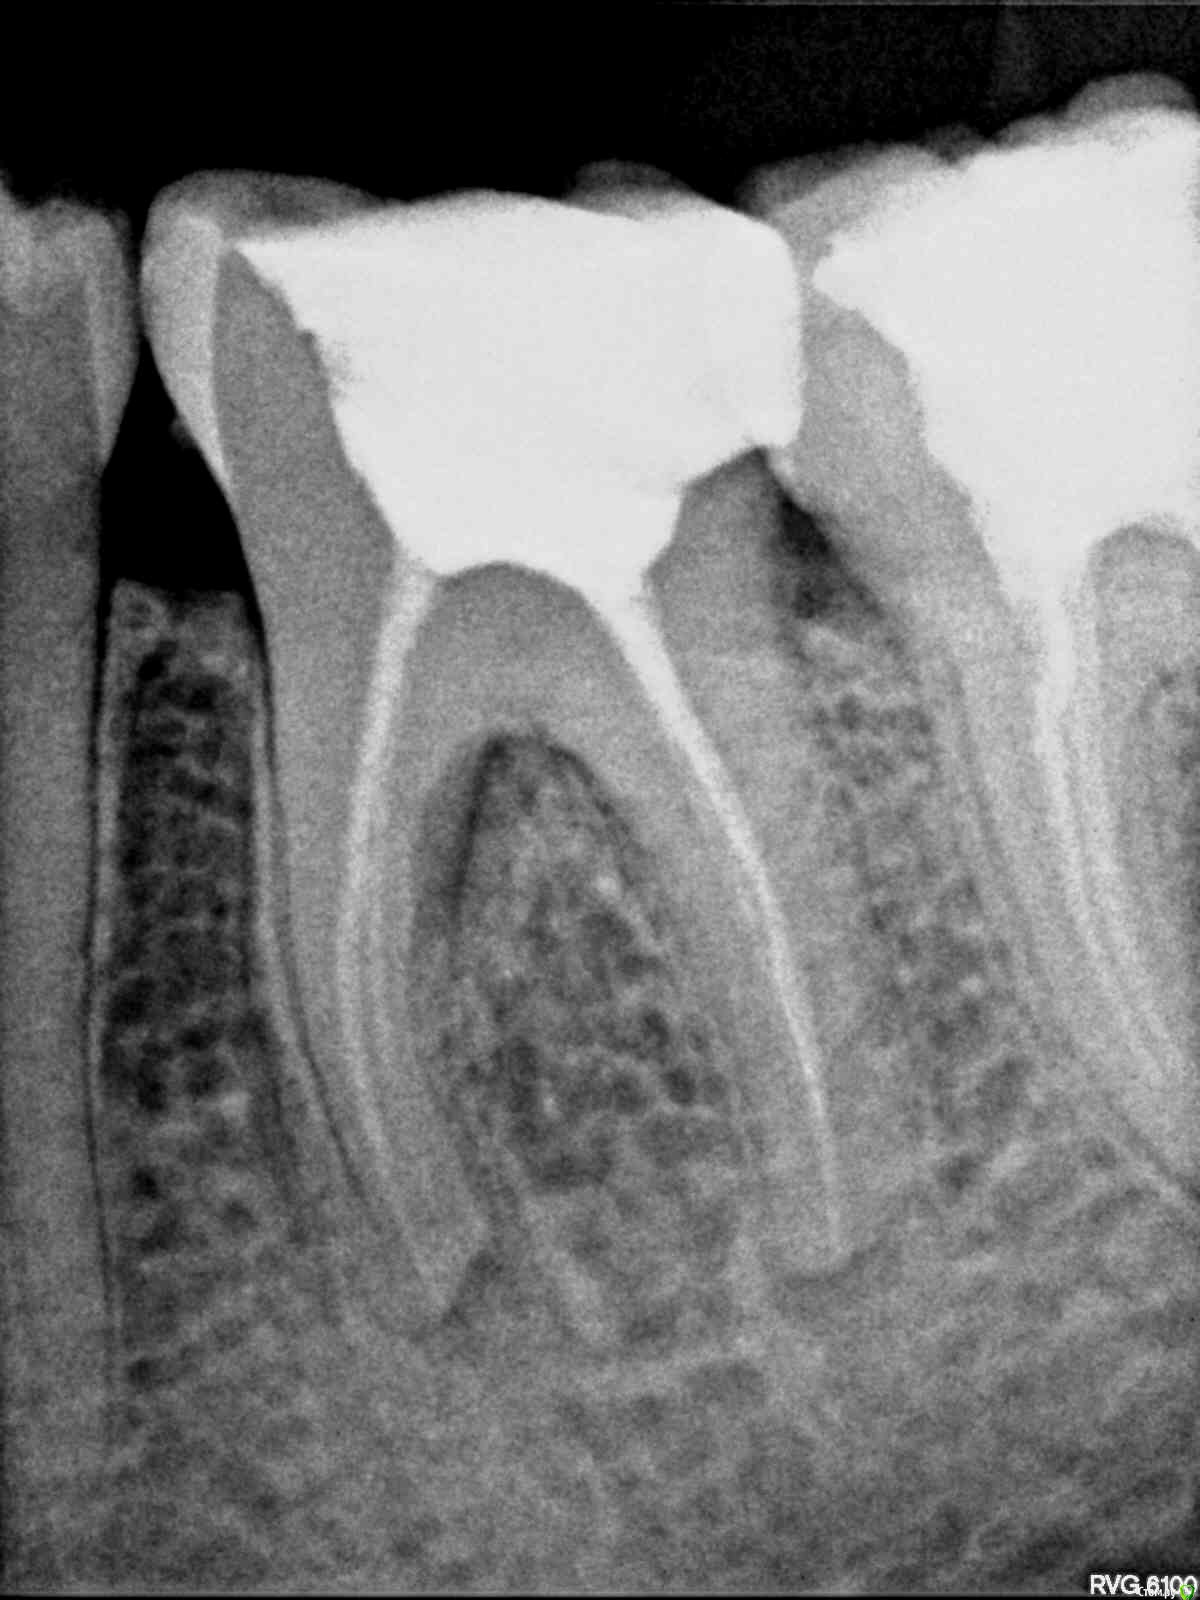

Alex_V6 Опубликовано 8 октября, 2015 Поделиться Опубликовано 8 октября, 2015 Здравствуйте !История такова , в июне обратился в клинику по поводу удаления зубов мудрости , там сделали снимок , обнаружили темные области под 36 зубом ( он был пролечен уже лет 10 тому назад, не болел абсолютно ) сказали что там инфекция и нужно заново пролечить каналы, я согласился. все почистили и подготовили под установку коронки , в итоге 2 недели назад почуствовал сильную боль внизу челюсти сделал снимок .. врач кто собственно перелечивал каналы говорит что мол , не получилось убрать инфекцию и она где то там , и надо теперь делать либо резекцию верхушек , либо удалять зуб, а мой знакомый стоматолог сказал что пролечивание было сделано плохо , материал вывели за пределы зуба и поэтому все проблемы ..Помогите пожалуйста разобраться, действительно ли воспаление из за врачебной ошибки , плохой работы, или всему виной инфекция которая жила у меня 10 лет и видимо осталась внутри . Спасибо за помощь !!снимки прилагаю Ссылка на комментарий

anvladd Опубликовано 8 октября, 2015 Поделиться Опубликовано 8 октября, 2015 (изменено) Каналы запломбированы хорошо,материал конечно выведен за верхушку,бывает(верхушки корней были "разъедены"воспалением,судя по всему) а доктор видно,старался.Что вас в данный момент беспокоит? Чем запломбированы каналы? Изменено 8 октября, 2015 пользователем anvladd Ссылка на комментарий